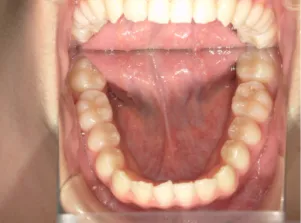

治療中➁小3:9y8m QH、BH、前歯並び替え終了

モノブロック装置(筋機能的咬合誘導装置)スタート